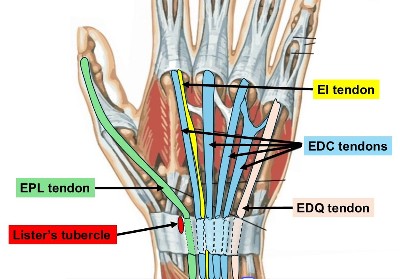

- The EPL = Extensor Pollicus Longus tendon runs along the back of the wrist to the thumb and wraps around Lister’s tubercle, using it as a pulley.

- This applies particularly when the fracture involves Lister’s tubercle – a prominence on the back of the radius around which the EPL changes direction

2. EI to EPL tendon transfer.

- There are 2 tendons that extend the Index finger ( EI & EDC tendons)

- The EI tendon is available for transfer because the EDC tendon to the index finger can still provide normal index finger extension on its own

- The Extensor Indicis (EI) tendon (used to extend the index finger) is redirected to take over the function of the EPL.